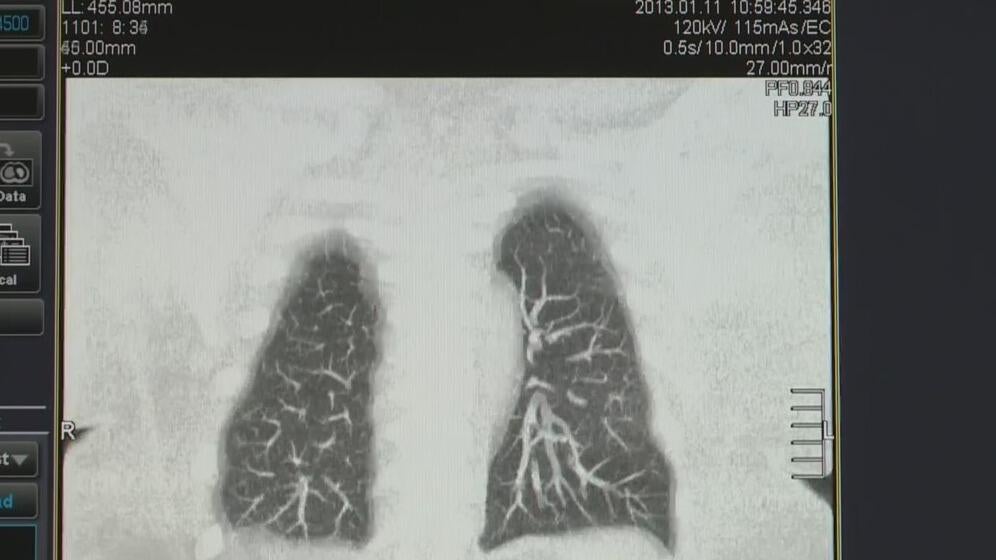

Study finds only 18% of people eligible for lung cancer screenings actually get them

A study found that only 18% of people who are eligible for lung cancer screenings actually get them.